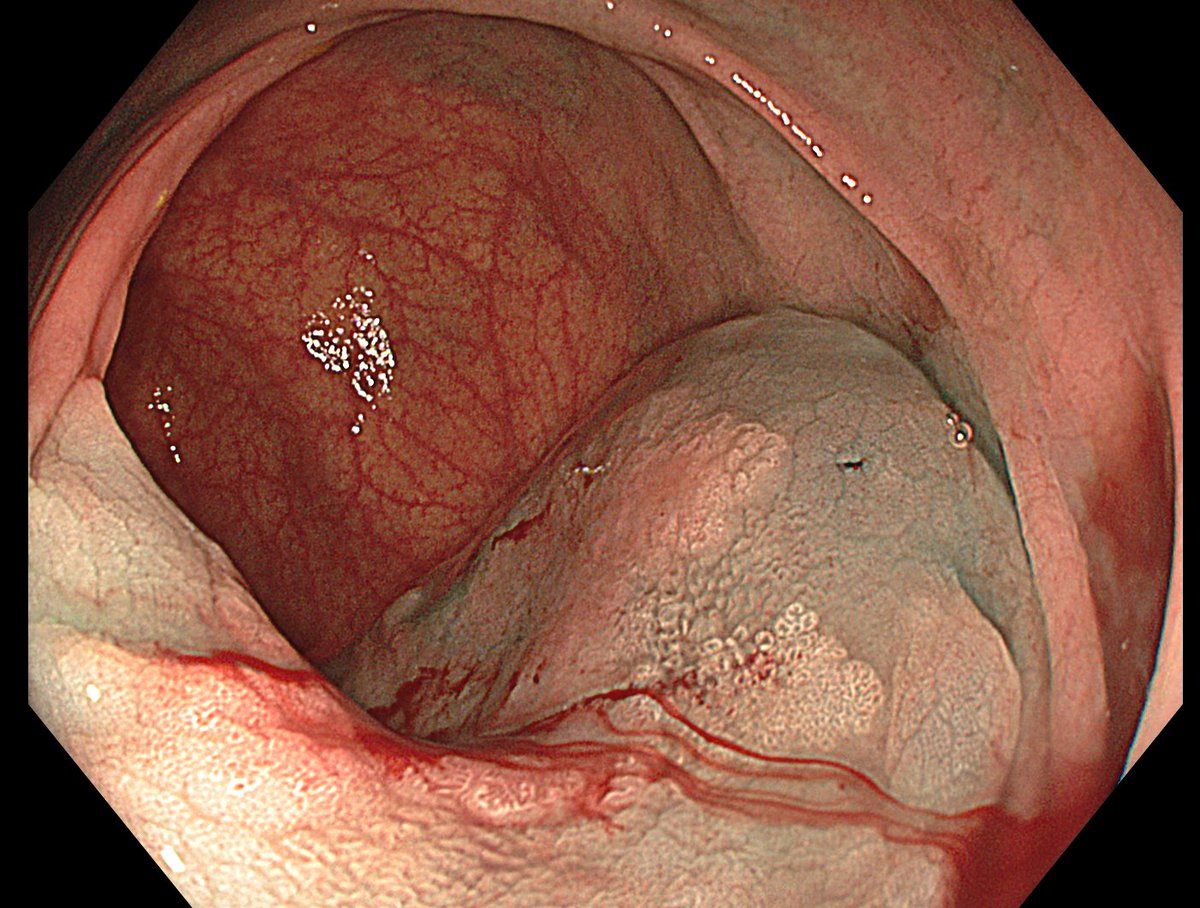

1. Antrum, low grade dysplasia. Removed via ESD. Specimen 43x32mm / dysplasia 20x13mm. R0